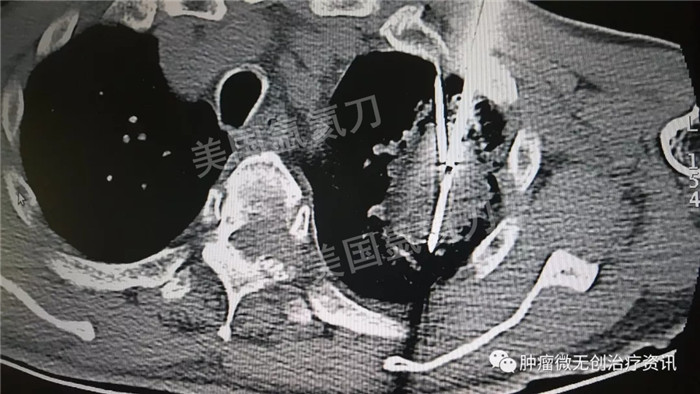

民航总医院氩氦刀冷冻消融治疗肺癌

63岁男性患者,发现左肺占位1天入院,伴多发骨转移及肺内转移,行氩氦靶向治疗减瘤,同时穿刺取病理活检。